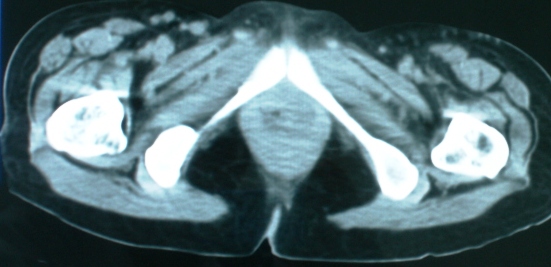

以下是引用zsl6918在2008-11-4 19:14:00的发言:[br]多发转移性改变,子宫改变不除外为原发灶